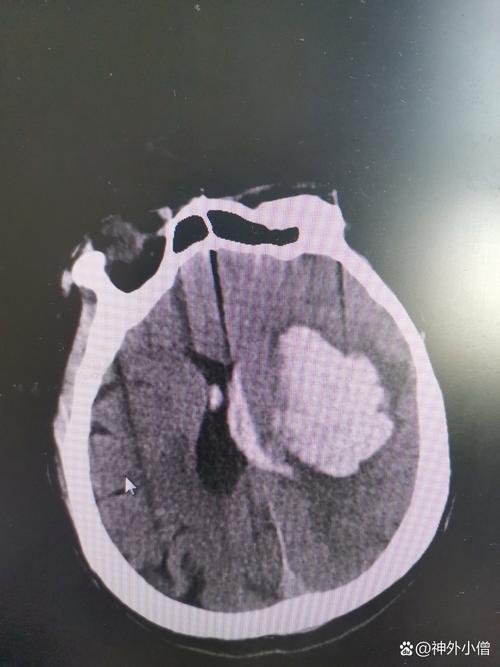

- 头颅CT/MRI:明确梗死的部位和范围。

- 血管检查(CTA/MRA/DSA):查看脑血管是否有狭窄、闭塞、动脉瘤或畸形。